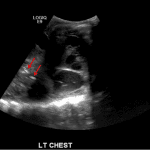

- Large, complex, multiseptated left pleural fluid collection

- Adjacent airspace consolidation in the left lung with air bronchograms

Pneumonia and empyema

Large, complex, multiseptated left pleural fluid collection with adjacent airspace consolidation, concerning for pneumonia and empyema. No discernible right pleural effusion.

- Worry about a complicated effusion (which may represent empyema, hemothorax, or malignant effusion depending on the clinical scenario) if the fluid collection has hyperechoic areas or if it contains internal septations

- As the lung fills with fluid, the only remaining air is in the bronchi, which produces air bronchograms – these appear as punctate and linear echogenic foci within the lung (see annotated image #3)

- Also, when densely consolidated, the lung becomes more discretely visible and takes a liver-like appearance, referred to as “hepatization”